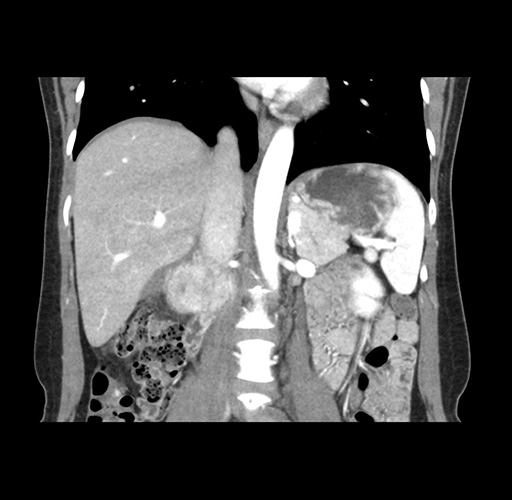

Imaging Analysis

Look through the patient's CT scan to identify any areas of concern for the necessary procedure.

Based on your CT findings, which issue(s) would give reason for "planned slowing down moment(s)" in this case?

Considering a standard left lateral sectionectomy procedure, what step(s) of the operation would you do differently in this case ?